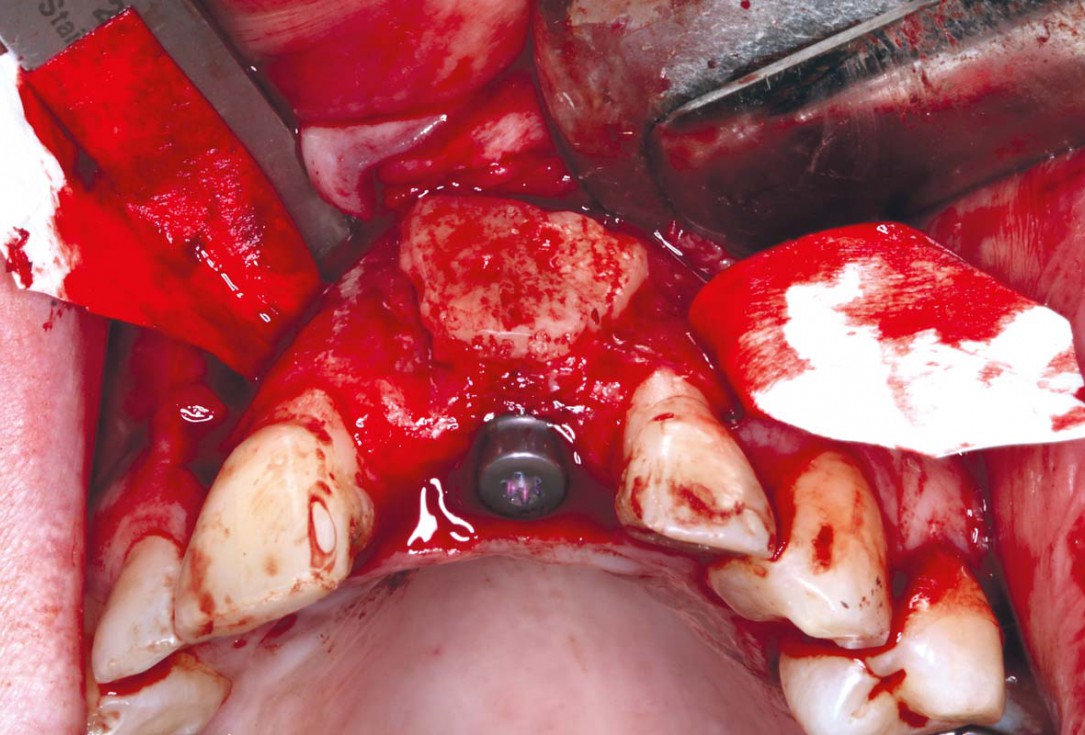

25/35 - GBR at the time of the implant placement - added cerabone® 0.5 cc small particles to increase the convexity and insure stability of the soft tissue. Jason® membrane stabilised with titanium pins and sutured palatallyBlock grafting in the aesthetic zone with maxgraft®, Jason® membrane and cerabone® - Dres. H. Maghaireh and V. Ivancheva

26/35 - GBR at the time of the implant placement - added cerabone® 0.5 cc small particles to increase the convexity and insure stability of the soft tissue. Jason® membrane stabilised with titanium pins and sutured palatallyBlock grafting in the aesthetic zone with maxgraft®, Jason® membrane and cerabone® - Dres. H. Maghaireh and V. Ivancheva